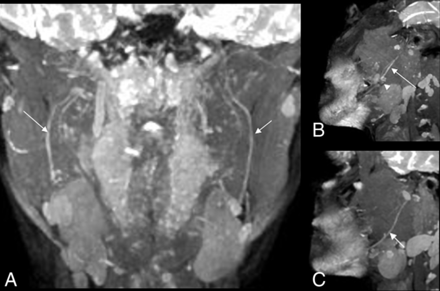

Coronal 3D PSIF images were chosen to perform measurements on because they produce nerve-selective imaging.20 Two readers with 20 and 5 years' experience in radiology, respectively, independently performed the measurements after a training set of 6 scans that included both case and control patients. The readers were blinded to the clinical history or prior MRN report. For the control group, a predefined bony landmark was used to identify both nerves for measurement. The midmandibular canal was chosen because the midlingual nerve can be easily identified medial to the medial cortex of the mandibular ramus, and the IAN lies within the bony mandibular canal (Fig 3A). Nerve thickness was recorded by measuring the maximum transverse dimension of the IAN in the midmandibular canal and the LN in its midcourse. T2 signal intensity was recorded in the same area by drawing a freehand ROI on each nerve (Fig 3B). In patients who underwent tooth extraction (the study group), the measurements were performed at the site of the most visible abnormality of the affected nerve. This was followed by calculation of T2SIR (SI nerve ÷ √SI nerve)21 and CNR (SI nerve − SI pterygoid muscle ÷ √SI nerve) for each nerve in both groups. All data points, measurements, and calculations were recorded on a spreadsheet for data analysis.

Coronal 3D PSIF images showing A, localization of the site of the LN and IAN (short and long arrows, respectively) and B, signal intensity measurements on both sides.